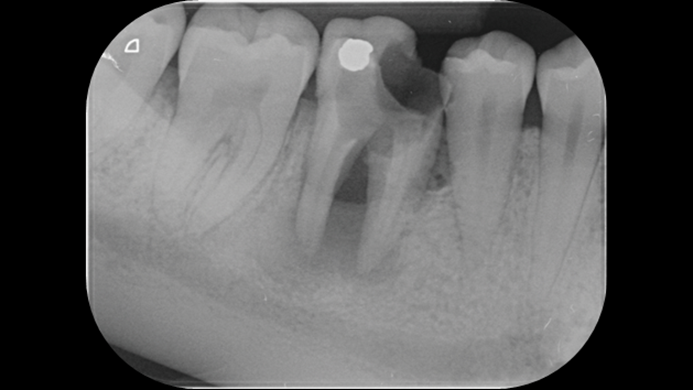

Clinical case: # 46 implant placement & GBR using i-Gen membrane for significant vertical resorption & mixed bone defect

- Courtesy of Dr. Iulian Filipov, Romania -

AnyRidge, mandibular posterior, i-Gen, resorption, bone defect, bone regeneration, space management, #46, GBR, Dr. Iulian Filipov

AnyRidge implant system, i-Gen